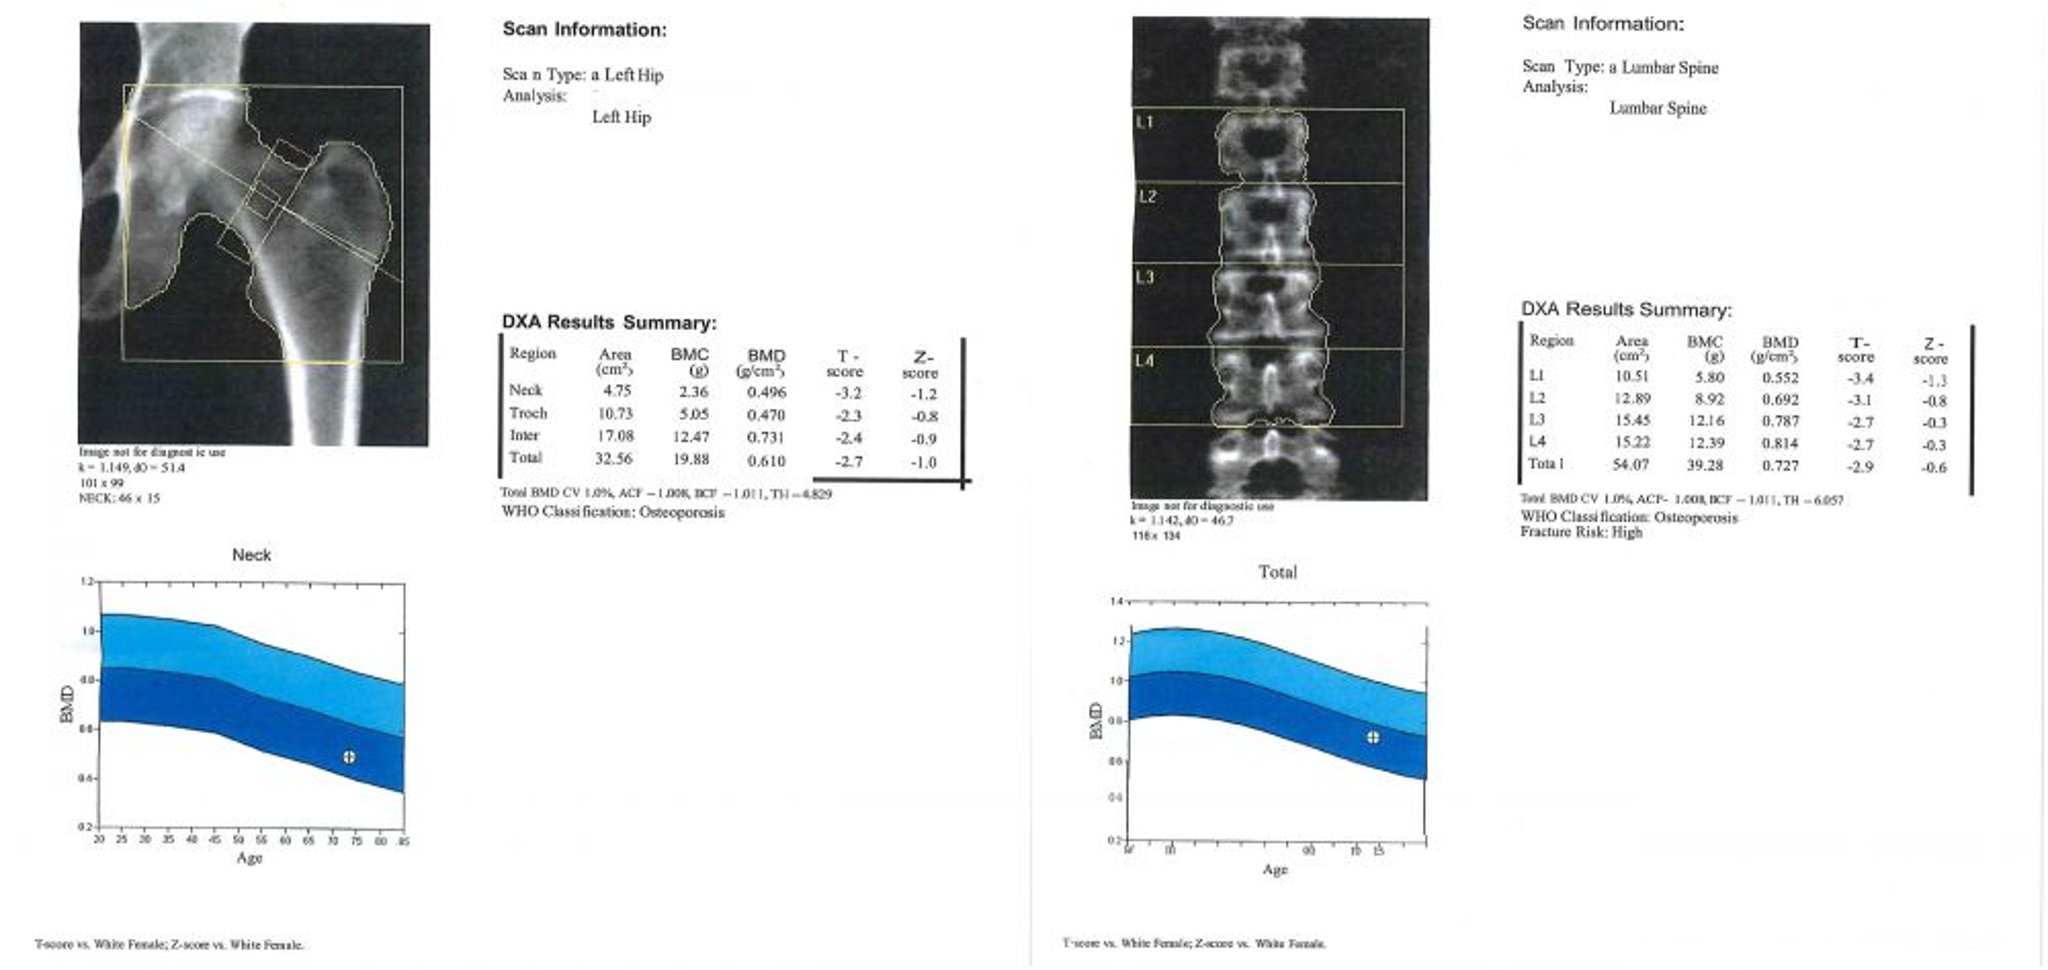

ДЭРА-сканирование

Данное изображение является примером результата ДЭРА-сканирования. На графике область светло-голубого цвета представляет собой остеопению, а темно-синяя область ─ остеопороз. Показания пациента представлены знаком «+» внутри круга на каждом графике.

Image courtesy of Marcy B. Bolster, MD.